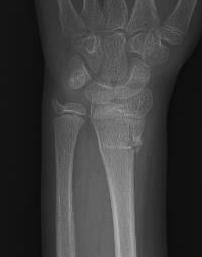

Types

Central growth arrest - ulna sided overgrowth

One sided growth arrest - angular deformity of the distal radius

Ulna sided overgrowth

Wrist deformity / dysfunction / ulna sided pain